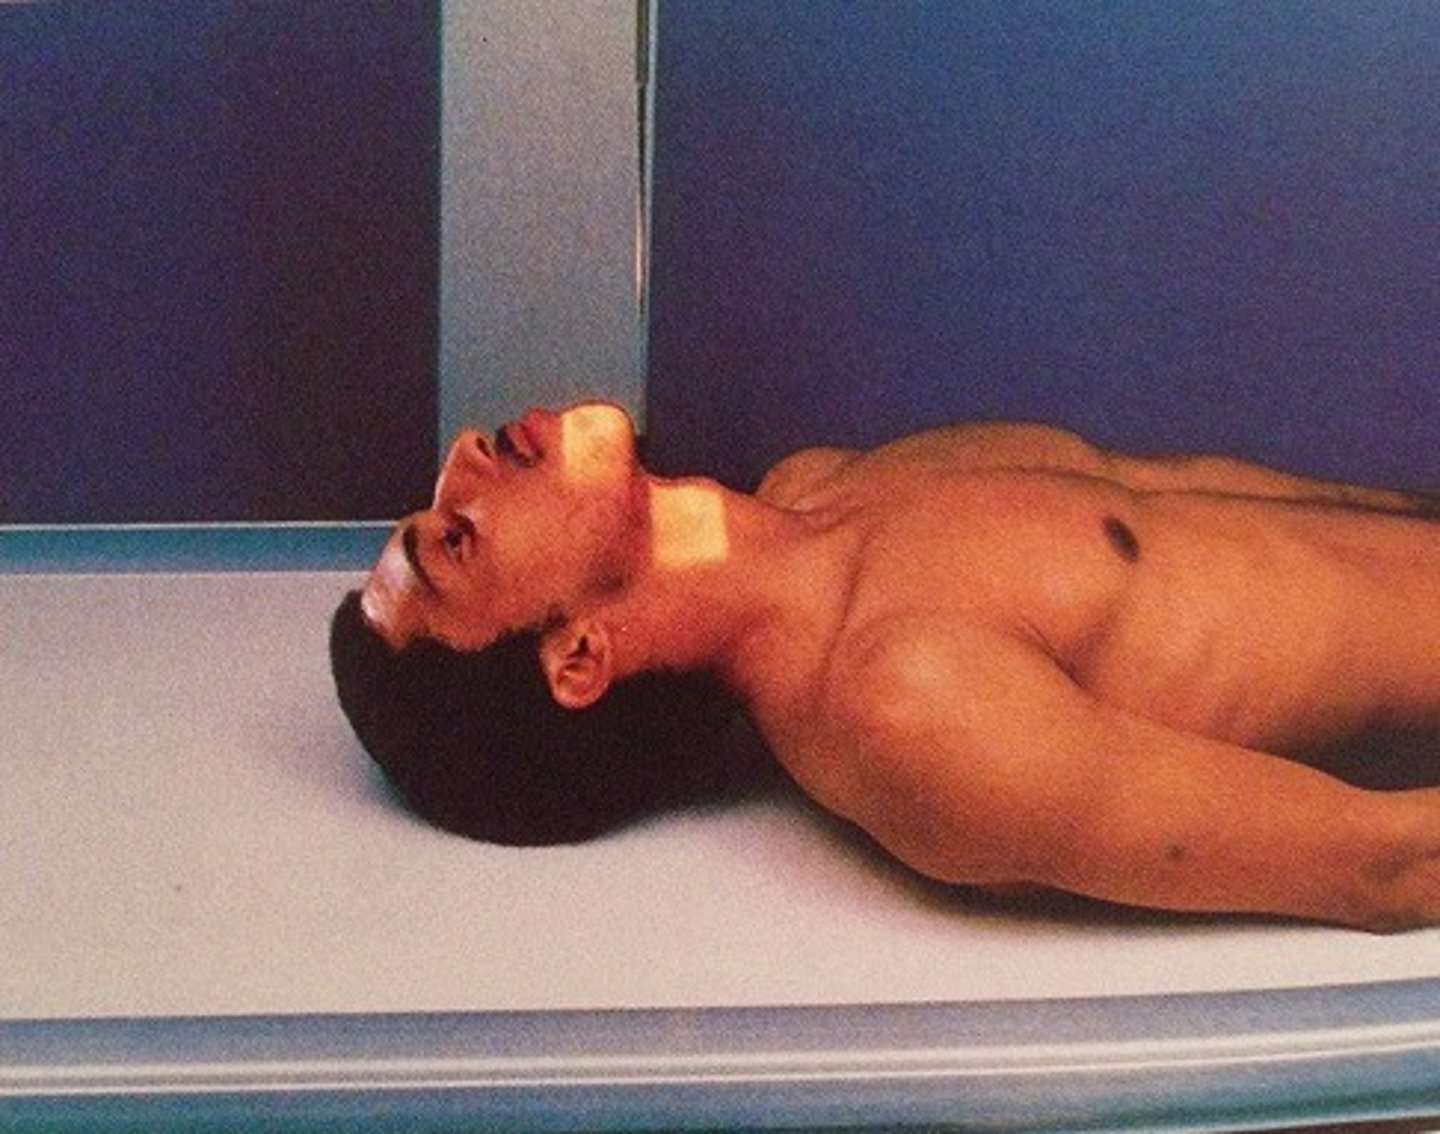

Go through the STAMPSBC list for the AP Fuchs C-spine

S - shielding around waist

T - 40 mAs @ 75 kVp

A - no angle

M - correct marker on correct side

P - laying on back, chin elevated so MML is parallel to beam

S - 40

B - suspended breathing

C - 10 x 12 lengthwise, can collimate to 7 x 7